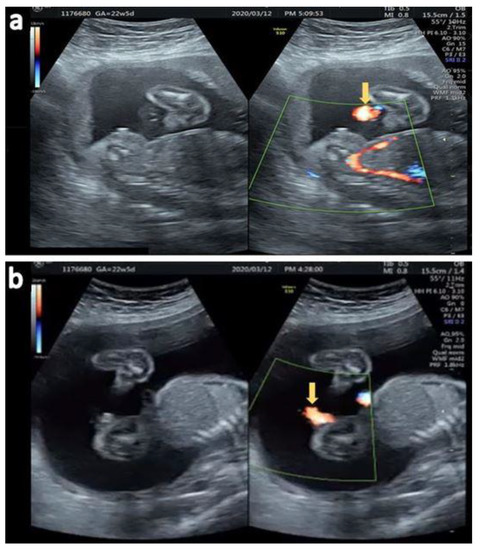

2.1. Case 1